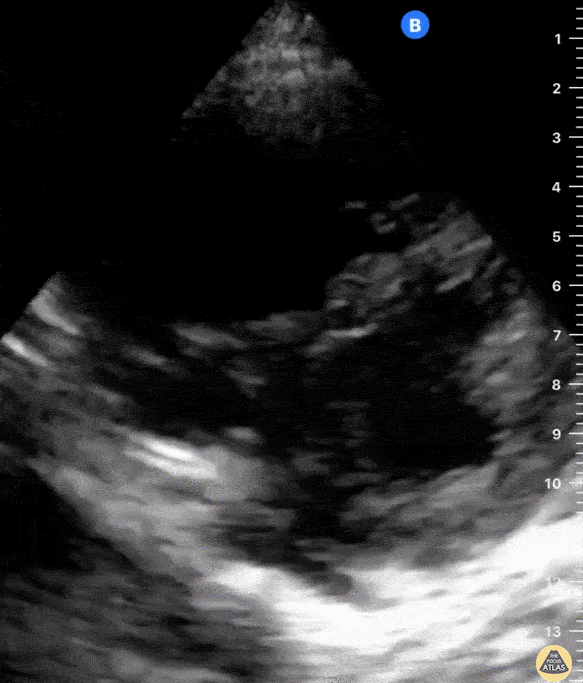

A 56-year-old female with history of metastatic breast cancer presented with acute shortness of breath. Physical examination was notable for hypotension, sinus tachycardia, raised JVP, and mild respiratory distress. There was no evidence of lower extremity edema and chest xray was unremarkable. POCUS showed no B lines on lung views. Cardiac views (seen here) were notable for a hypokinetic and dilated RV with flattening of the interventricular septum creating a D shaped LV during systole. These findings are consistent with high right ventricle and pulmonary artery pressures in the absence of pulmonary artery stenosis. Specifically, a D-shaped LV during diastole reflects RV volume overload; a D-shaped LV during systole reflects RV pressure overload. RV pressure overload can be seen in massive and submassive pulmonary embolism (PE) and this patient was diagnosed with a submassive PE; findings confirmed by CT angiography. In this instance, POCUS enabled prompt diagnosis and early initiation of therapeutic anticoagulation. Shahad Al Chalaby, MD. Highland Hospital. Alameda Health System Internal Medicine Residency Program. California, USA. shahad_Chalaby Katherine Farley, OMS4. Touro University. California, USA.